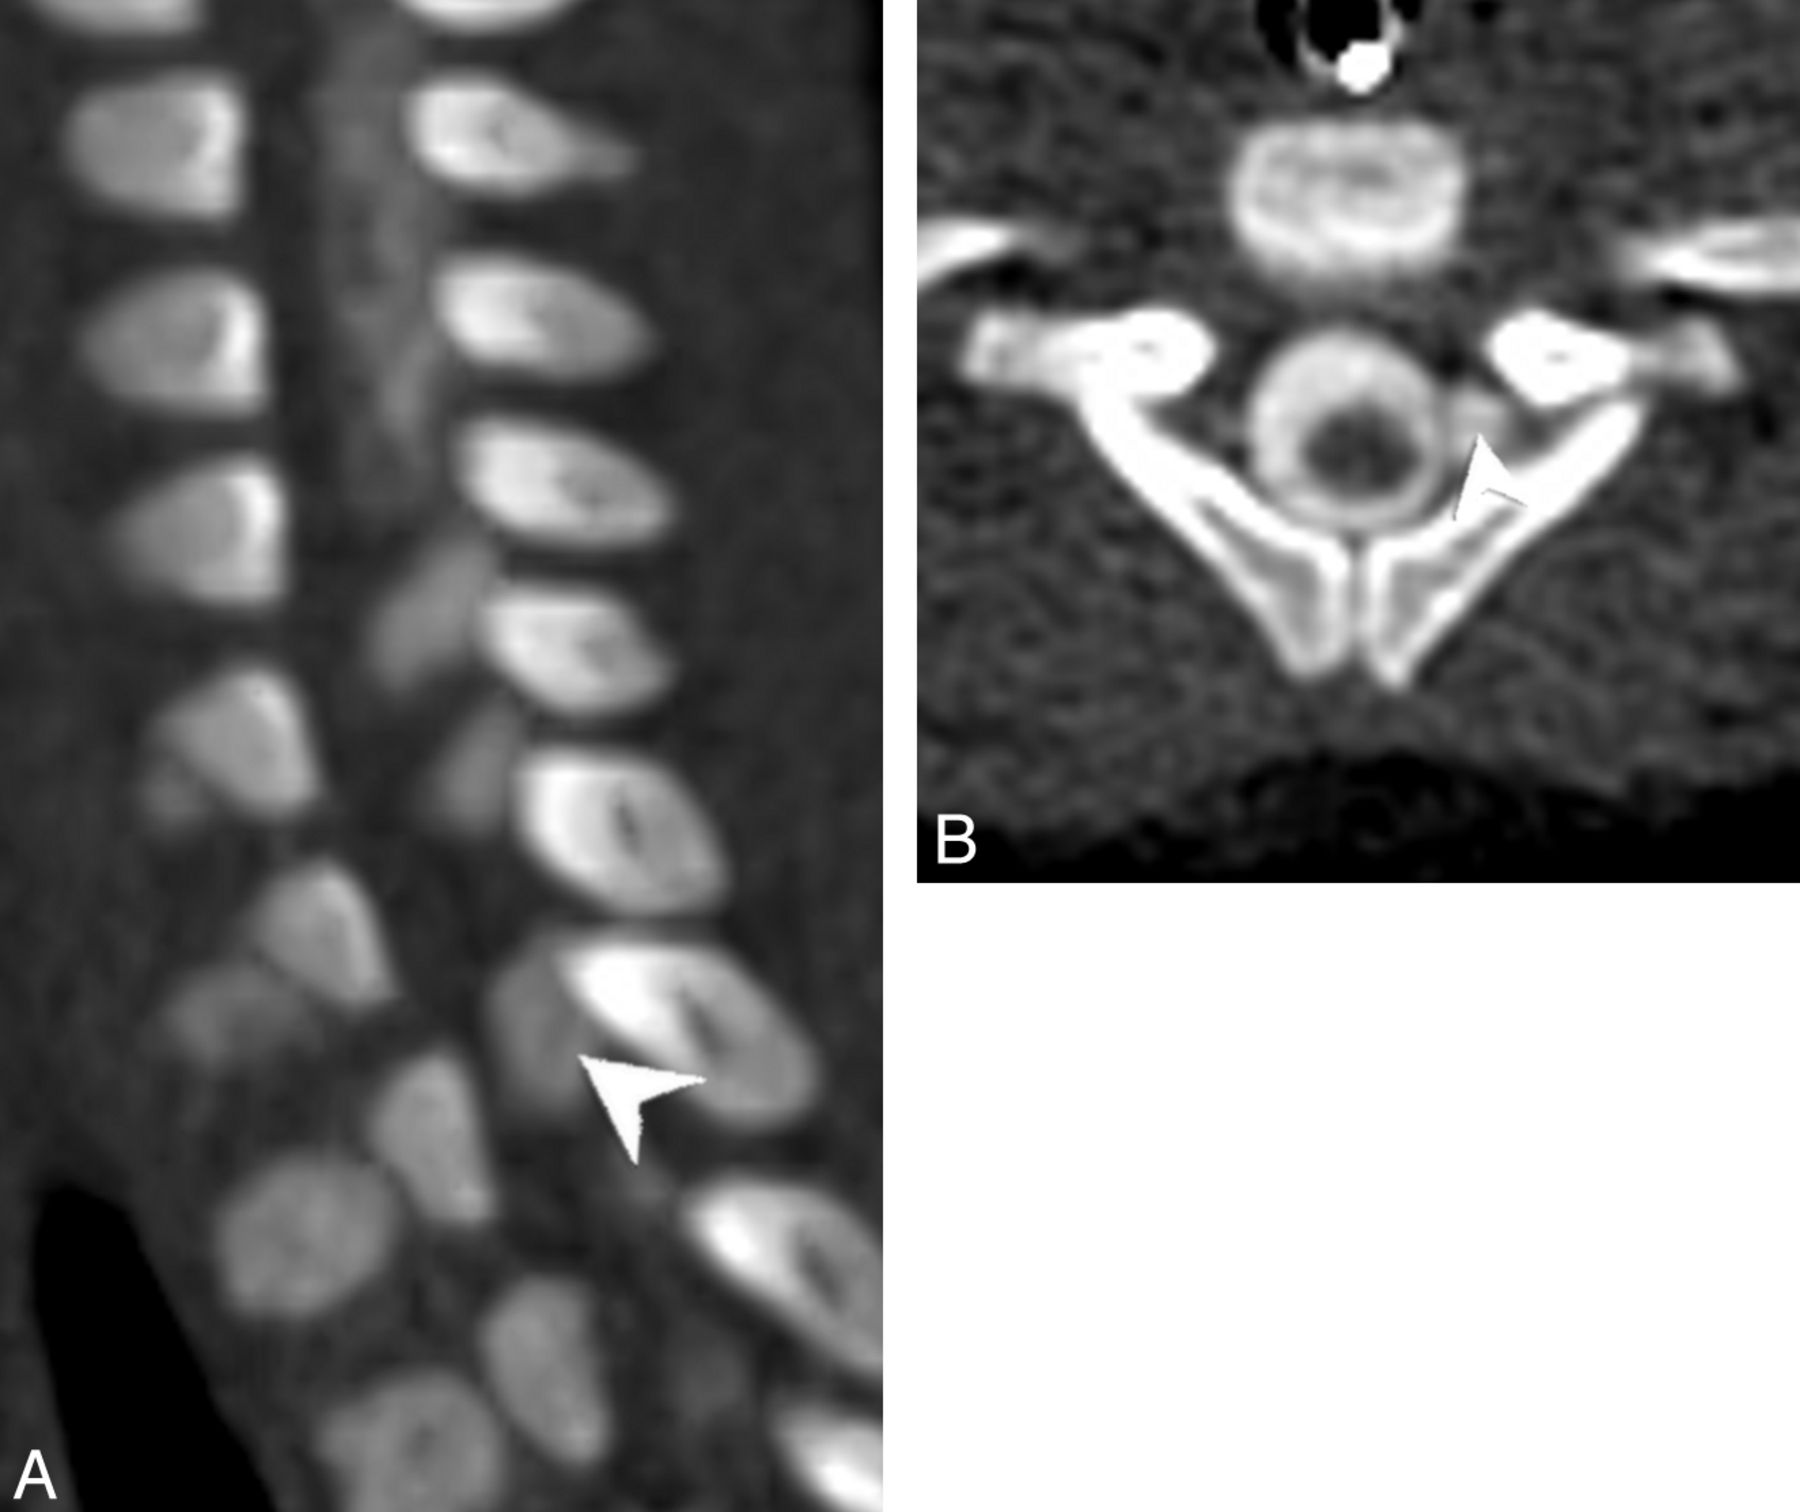

Two pediatric radiologists (with 7 and 8 years' experience, respectively) independently evaluated each imaging study and rated each root level from C5 to T1 according to the system in Table 1. Discrepancies were resolved by consensus analysis. Findings A and B (Figs 1 and 2) have previously been used as predictors of nerve root avulsion in infants.14 Finding C (Fig 3) has been described as a predictor in adults.19 Findings D and E (Figs 4 and 5) have been suggested to indicate partial nerve root avulsion.12

Axial (A), coronal (C), and left parasagittal (E) images from a CT myelogram and corresponding axial (B), coronal (D), and left parasagittal (F) images from an MR myelogram (B, D, and F) on the same patient demonstrating 3 consecutive left-sided pseudomeningoceles with absent rootlets at C7–T1 (arrows in A and B, arrowheads in C and D, arrows in E and F). Note the internal septa within the middle and lower pseudomeningoceles that can simulate intact rootlets on a single image.